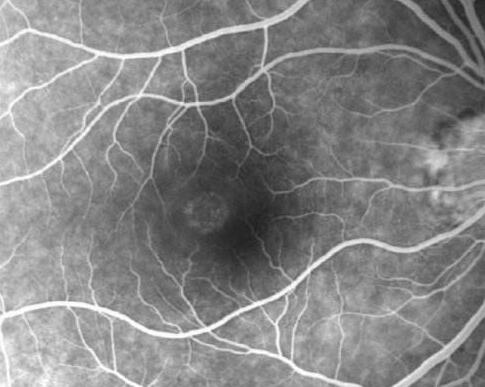

中渗